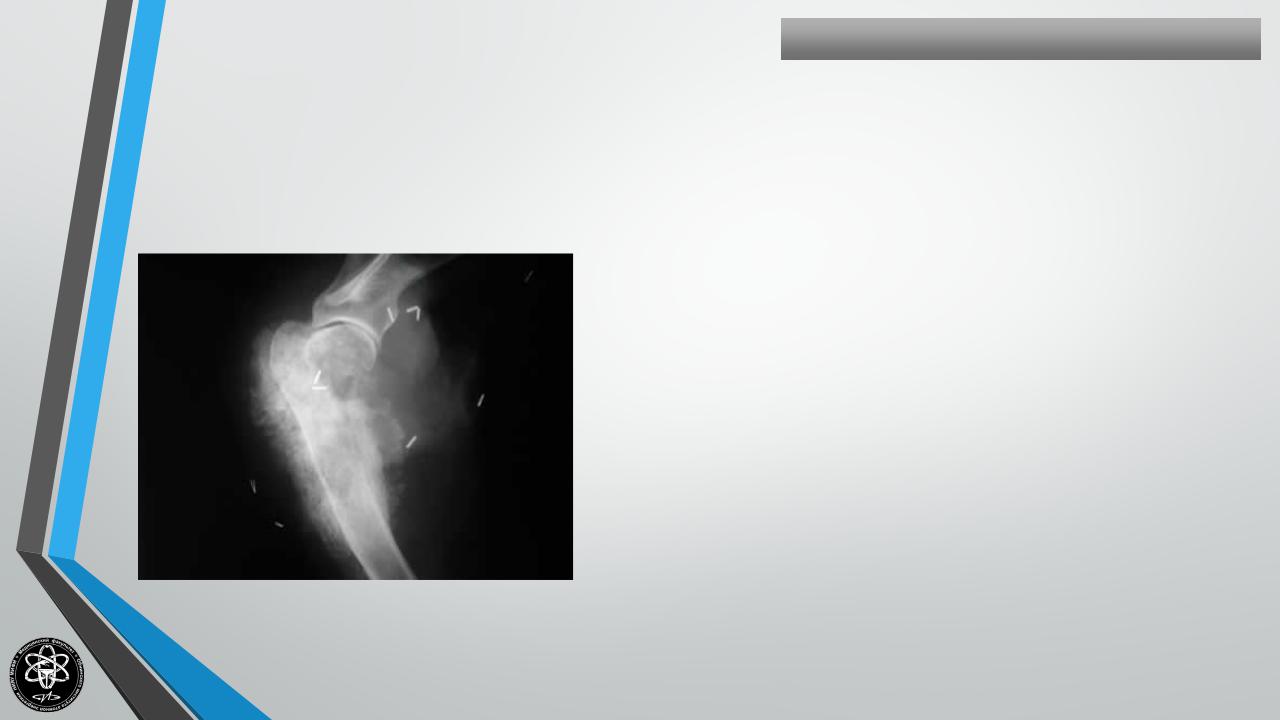

ОСТЕОГЕННАЯСАРКОМА

Частота — 23,6% всех костных опухолей и 46,5% всех

злокачественных опухолей.

Поражаемый возраст — 10-23 года, но наблюдаются и в

других возрастных группах.

Излюбленная локализация — дистальный конец

бедренной кости, большеберцовая, плечевая кости.

Чаще поражаются мужчины.

Клиническая картина — боль, быстрый рост, сосудистая

сеть в области опухоли, при аускультации можно

слышать шум над опухолью, местная температура

повышена.

Длительность течения — 6 месяцев-2 года.

Рентгенологически

остеолитическая

или

остеопластическая формы, “Козырек”, “спикулы”. Лабораторные сдвиги — СОЭ нарастает до 30-50 и

более

мм/час,

растет

щелочная

фосфатаза.

Метастазирует чаще в легкие.

Лечение

комплексное

хирургическое,

медикаментозное. Прогноз неблагоприятный.